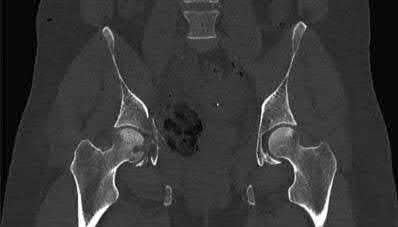

Question 12:

A 13-year-old obese male complains of left knee pain and a limp for 3 weeks. Radiographs are provided: He is able to bear weight with crutches. During physical examination, as the affected hip is passively flexed, into which position will the limb obligately deviate?

Correct Answer: External rotation

Explanation:

In slipped capital femoral epiphysis (SCFE), the proximal femoral epiphysis displaces posteriorly and inferiorly relative to the femoral neck. This altered anatomy leads to an obligate external rotation of the thigh during passive hip flexion, a classic physical examination finding.